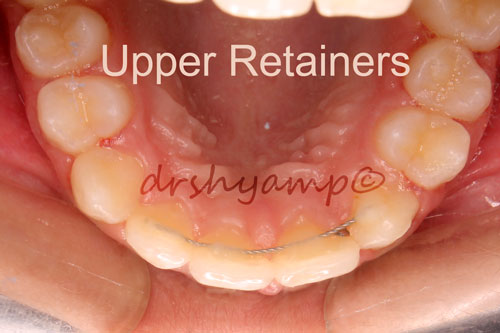

lower anterior teeth crowding

-

lower anterior teeth crowding

Correction of lower anterior teeth crowding